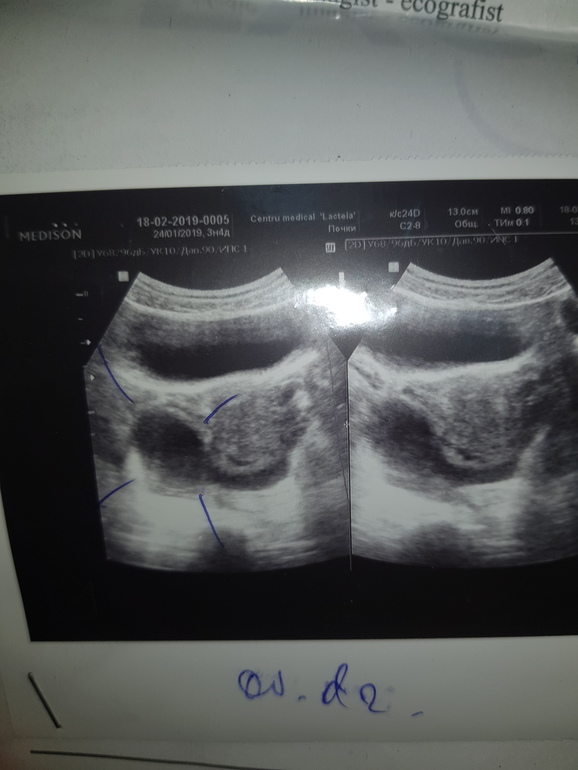

В этом месяце овуляцию не отслеживала, обычно на 16 день цикла. В этот раз начиная с 22 дц по25 дц делала тесты, много разных по паре раз в день ( да, я нетерпеливая🙈🙈) все были чистые...даже с обработкой... примерно на 23 дц почувствовала сильные тянущие боли , на 24 дц боли были прямо очень сильные, ношпа почти не помогла. В понедельник - на 26 дц- пошла на узи. Эндометрий 7-8, киста ( под вопросом фоликулярная) 45×40мм, жидкость 3-4 мл.

Узи если кто разбирается: